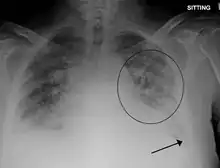

- Evidence of acute or worsening pulmonary edema (by physical examination or chest imaging)

The clinical symptoms from TACO are due to an excess of fluid within the circulatory system. As a result, there is increased pressure within the circulatory system, resulting in fluid moving into the surrounding tissues.[4] In the lungs, the extra fluid accumulates into the air sacs within the lung, causing difficulties in oxygen getting into the blood. This results in low blood oxygen levels and shortness of breath. In the arms and legs, the fluid accumulates in the tissues, causing swelling. This is most prominent in the legs due to the effects of gravity. Conditions that predispose to increased hydrostatic pressure (heart failure and renal insufficiency) or decreased oncotic pressure (liver failure, malnutrition, nephrotic syndrome) places individuals at increased risk for TACO.